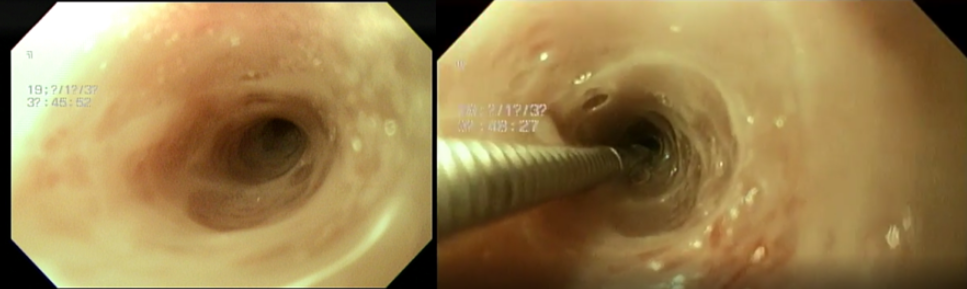

좌측 사진 - 확장 전의 식도 (6mm) / 우측 사진 - 1차 확장 시술 후의 식도 (12mm)

1차 확장 시에는 환자의 식도가 6mm에서 1mm 단위로 12mm 까지 확장을 진행하였습니다.

1차 확장술 이후 환자는 유동식 식이가 가능하였으나 아직 덩어리진 식이는 하지 못하였습니다.